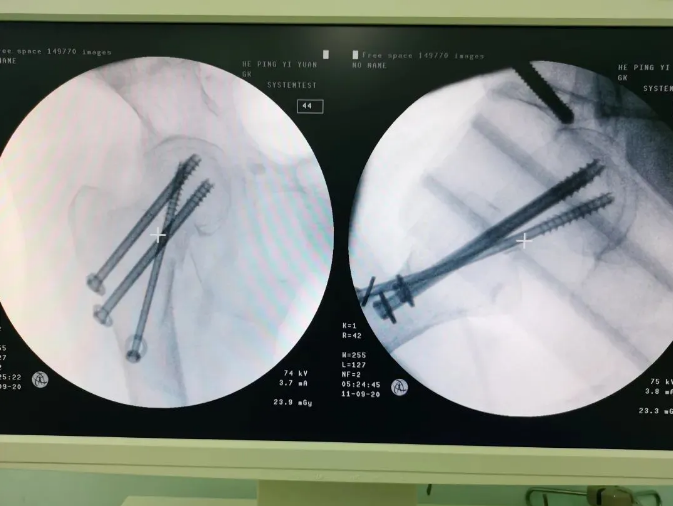

規劃入路

天璣機器人置入螺釘

螺釘置入后

天璣?骨科手術機器人的加入,能夠協助醫生為需要進行手術的患者提供更安全、優質、高效的醫療服務,幫助患者清除病灶,守護患者健康,提高患者生活質量。在天璣?骨科手術機器人的協助下,術中患者切口僅三個小孔,出血量少;術后陳婆婆經一段時間的康復訓練便可下床活動,目前已康復出院。